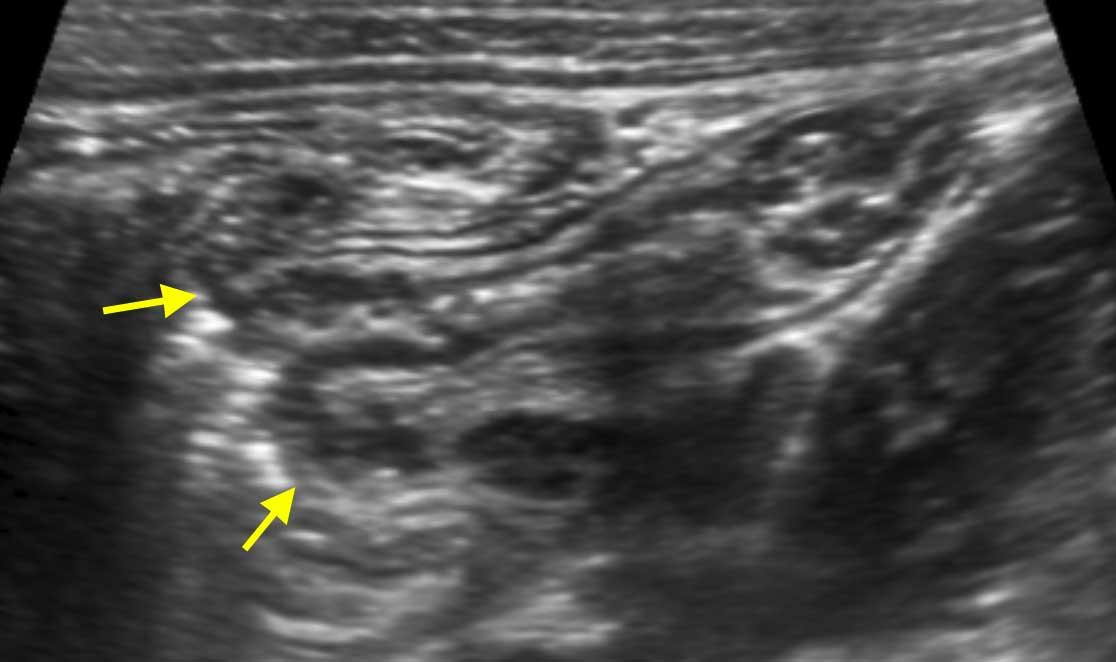

Intussusception

Đây là hình ảnh siêu âm của một trẻ 2 tuổi bị lồng ruột hồi manh tràng từng đợt, được khám trong khoảng thời gian giữa các cơn.

Hồi tràng với nhiều mảng Peyer sa vào manh tràng.